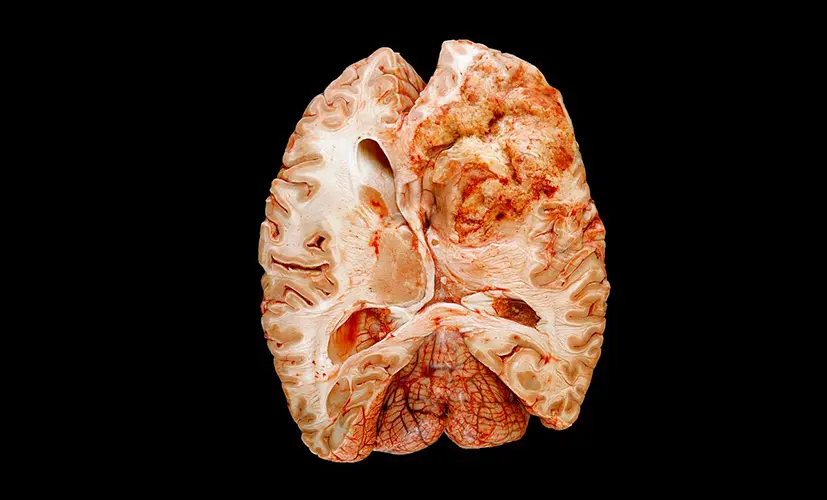

2. Dementia - the silent thief

Untreated cognitive decline can evolve into dementia. It may start as occasional forgetfulness, but before you know it, the condition has spread, impairing judgment and daily function. Patients describe the mental haze as a fog they can't escape. Most are diagnosed too late-when little more can be done.